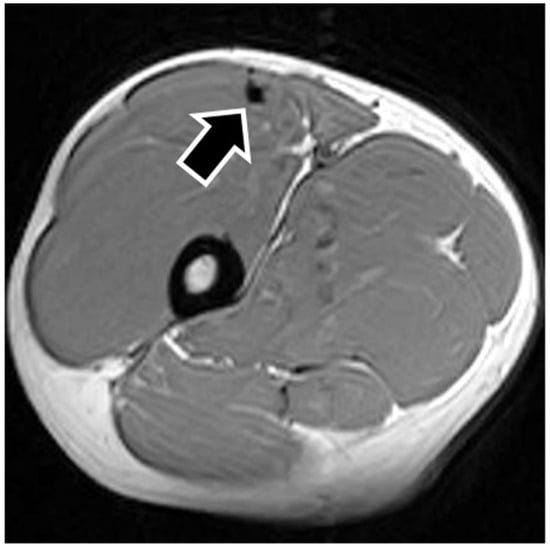

MRI findings are shown in Table 1. In eight of the RF strain injuries, a low signal area was noted in the central tendon (Figure 2). In four of the RF strain injuries, a low signal area was noted in the myofascial junction of the RF (Figure 3). In four of the RF strain injuries, the axial T1-weighted image did not show a low signal (Figure 4). The longitudinal range of the injured region in the 12 RF that showed a low signal area in MRI was approximately 8.8 cm (range, 4–17 cm). When the injured part was limited to the central tendon, the longitudinal range of the injured region was approximately 10.5 cm (range, 5–17 cm).

The MRI of a grade 1 strain is of a feathery appearance. Hemorrhage and fluid around the central tendon greatly suggest an acute grade 2 strain. In chronic or healing RF strains, there may be a fibrous encasement of the central tendon, characterized on MRI as T1 and T2 linear low signal around or adjacent to the central tendon [7]. The MRI showed a low signal area in this study so that the central tendon injured RFs were speculated as grade 2.

Figure 2. Pseudocyst of the central tendon. The figure shows an example of central tendon injury. The axial T1-weighted image shows a low signal surrounding the central tendon (black arrow), representing fibrous encasement.